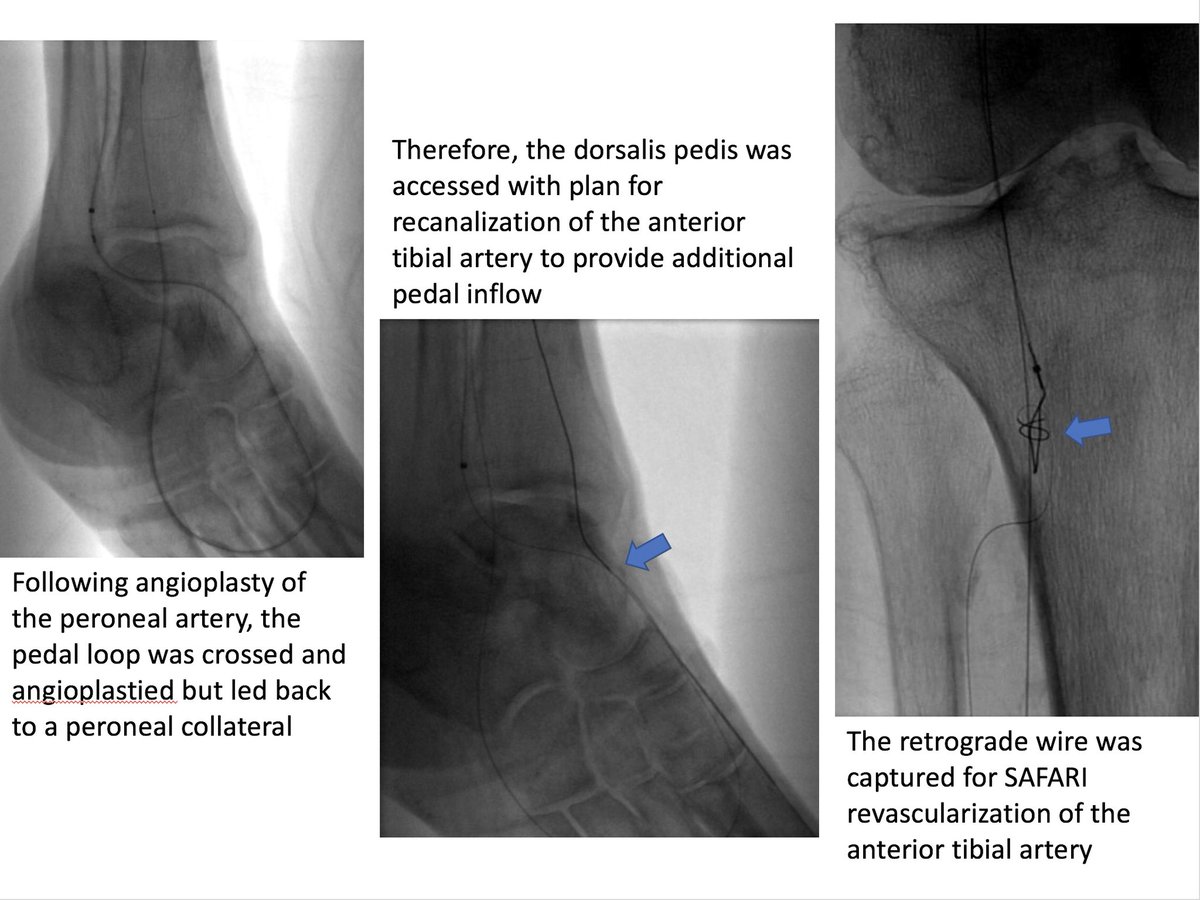

Active R4 patient limited at her full time job, losing sleep at night. Motivated to fight through pain, but needs help. Amazed at how well she functioned like this. She'll do awesome now! Shout out to @keithppereira for the support during the case! #CLIFighters #MyLegMyLife